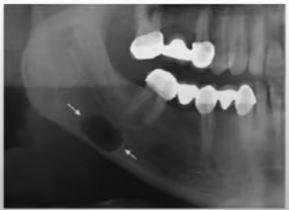

What are the radiological features of a keratocyst?

\* Well defined radiolucency \* Can be unilocular or multilocular \* Typically found in the posterior of the mandible (thinking logically, the 3rd molars are commonly abscent, hence this is why keratocysts could be most commonly found here)

Describe the management of cysts

\* Enulcleatuion involves the complete removal of the cyst. \* Incomplete removal can lead to recurrence. \* Marsupulization can be used if there is a high risk of IAN damage or mandibular fracture. This is where a surgical window is created allowing the contents to drain. This is sutured open and can be maintained with a packing material. \* The enucleation can then take place once the cyst has decreased in size